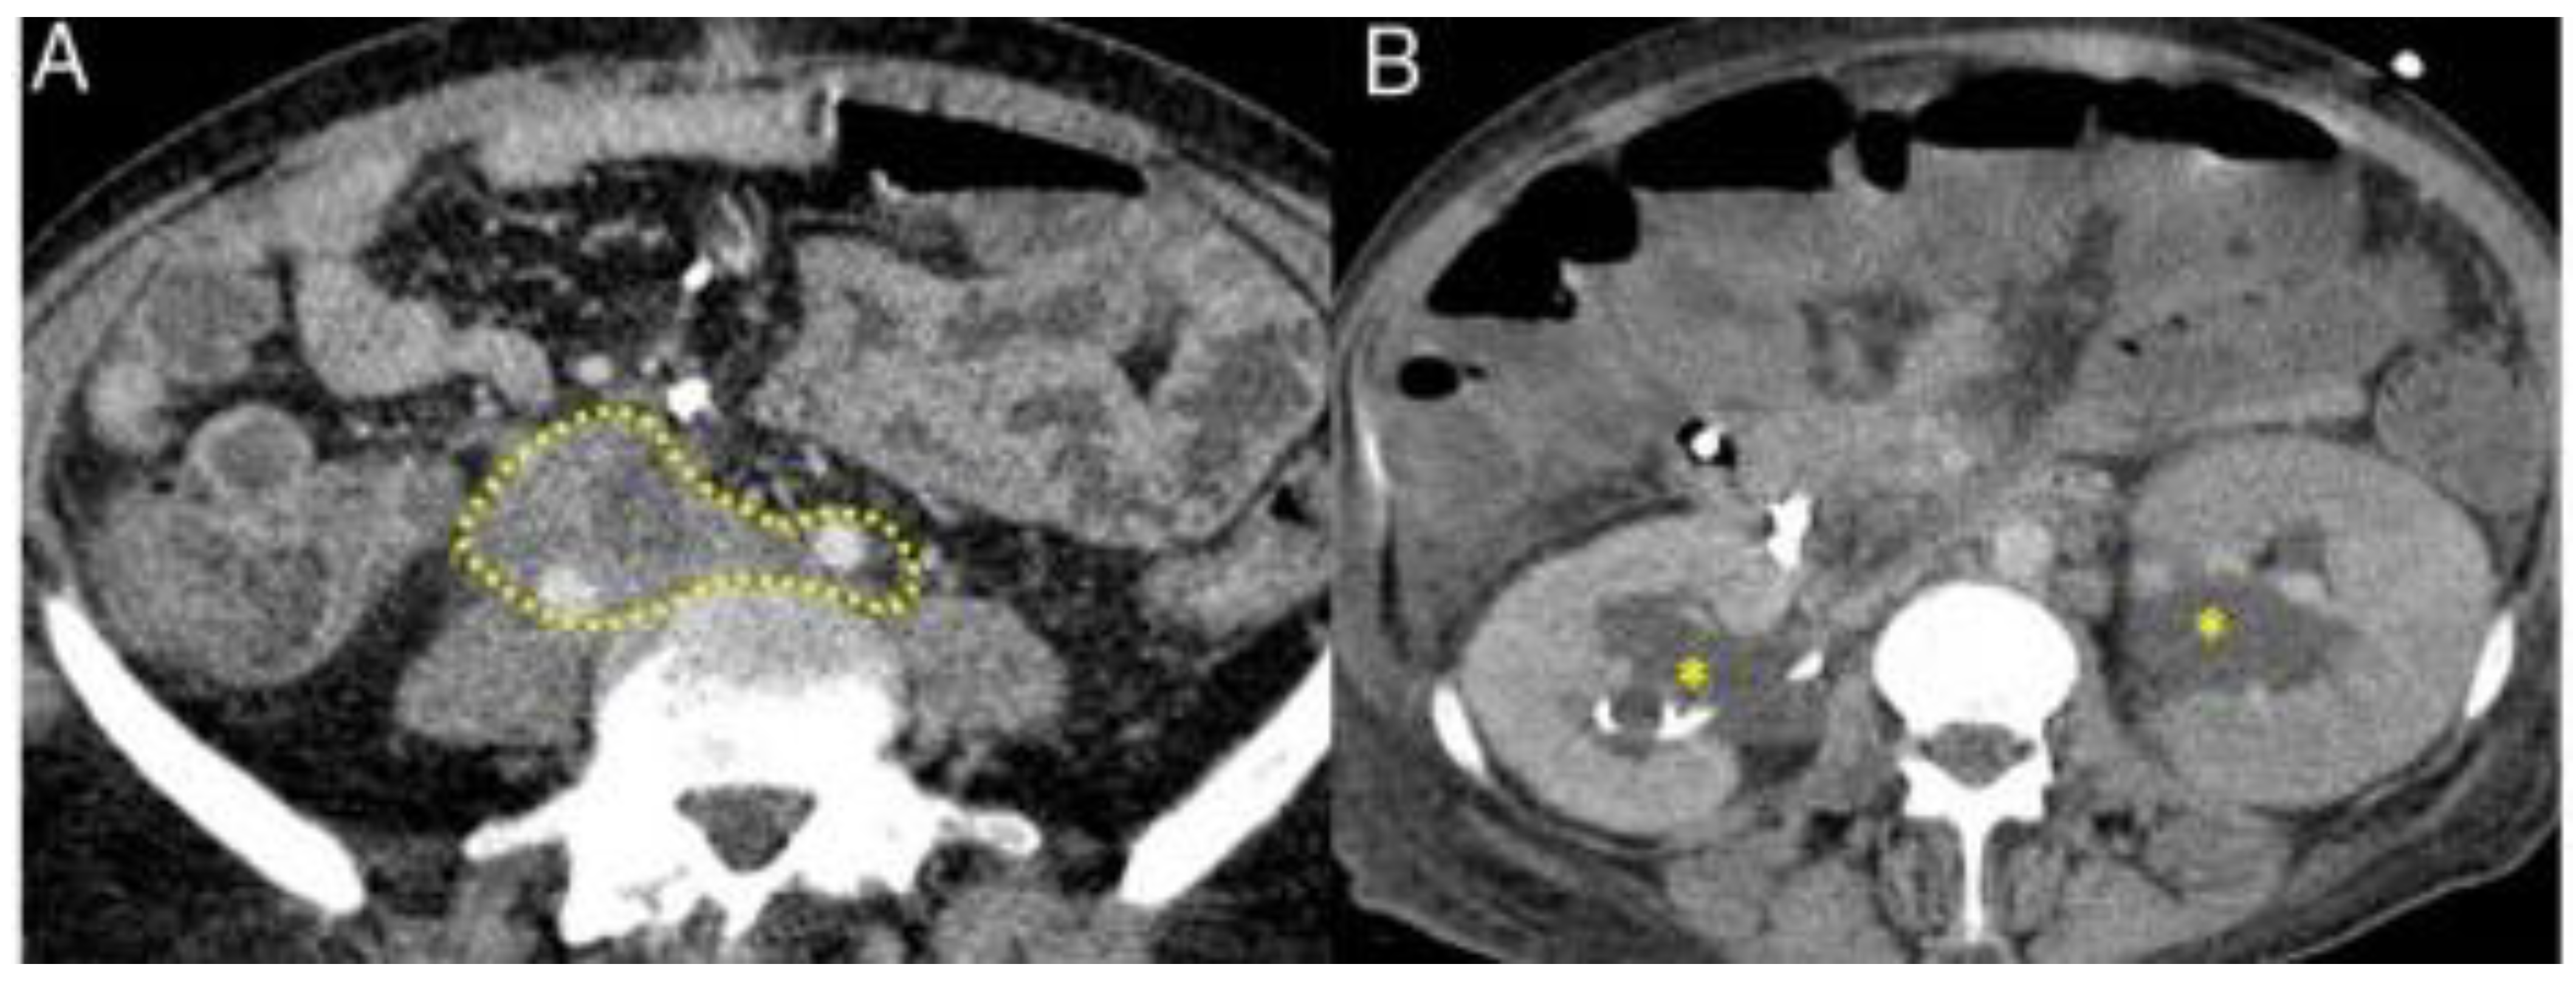

3.2.5. Retroperitoneum